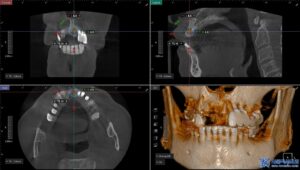

무절개 임플란트는 컴퓨터 분석을 통해

미리 계획된 경로를 따라 식립하기 때문에

절개가 필요하지 않고 출혈이 적으며

회복 속도가 빠릅니다.

또한, 위 사진처럼

수술가이드를 제작하여 오차 없이

정밀한 위치에 임플란트를

심을 수 있기 때문에

성공률도 높아지게 됩니다.